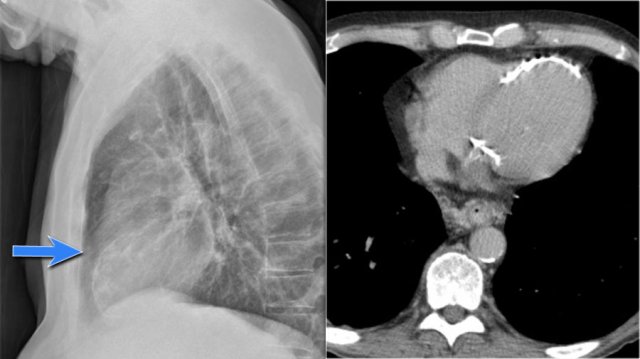

Hidden areas (3)

Here a pneumonia which was hidden in the right lower lobe mainly below the level of the dome of the diaphragm (yellow arrow).

Notice the increase in density on the lateral film in the lower vertebral region.

You may have to enlarge the image to get a better view.